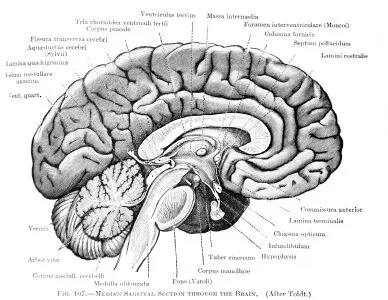

According to Health Canal, researchers at the Georgia Institute of Technology are seeking a better understanding of the brain’s inner workings and the changes brought about by injury. Through this research, they are not only attaining knowledge of the brain’s many complex mechanisms, but also are coming up with better treatments for brain injuries and disorders, afflictions that greatly interest the Atlanta traumatic brain injury attorneys at The Law Offices of Wayne Grant, P.C.

One team is researching the effects of electrical and light stimulation on the brain and its possible usage to reduce or eliminate seizures associated with epilepsy. Two million people in the United States are afflicted with the disorder. Seizures occur when nerve cells in the brain fire abnormally and excessively. The stimulation techniques, if valid, could help patients on whom drug therapies do not work. Experiments will be conducted on an animal model that is experiencing temporal lobe epilepsy.Read more…